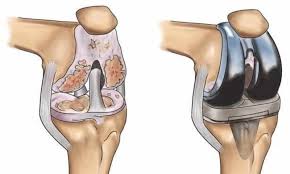

Several orthopedic conditions can lead patients to consider robotic joint replacement in Indore. Osteoarthritis is one of the most common causes of joint damage. In this condition, cartilage gradually wears away and causes severe pain and stiffness in the joint. As the joint deteriorates, movement becomes difficult and daily activities become uncomfortable.

Other conditions such as rheumatoid arthritis or traumatic injuries may also damage joint structures. In some cases, patients develop joint deformities that affect alignment and stability. When these conditions become severe and conservative treatments fail, an orthopedic specialist may recommend robotic joint replacement surgery. This procedure helps restore joint movement and reduce long-term discomfort.

Imaging tests provide additional information about the joint condition. X-rays reveal cartilage loss, bone changes, and joint alignment problems. MRI scans may help examine surrounding tissues and ligaments. These tests help the musculoskeletal specialist determine the severity of joint damage. Once the evaluation is complete, the surgeon can decide whether robotic joint replacement surgery is the most appropriate treatment.

Robotic technology offers several advantages in joint replacement procedures. One of the most important benefits is improved surgical accuracy. The robotic system allows surgeons to plan the procedure according to the patient’s specific joint structure. This personalized planning helps ensure precise implant placement.

Another advantage involves improved joint alignment during surgery. Correct alignment helps the artificial joint function more naturally after the procedure. Robotic assistance may also reduce unnecessary damage to surrounding tissues. These benefits support better joint stability and long-term performance of the implant. Many patients experience improved comfort and mobility after robotic-assisted joint replacement surgery.